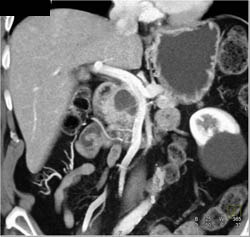

Encases Celiac Axis